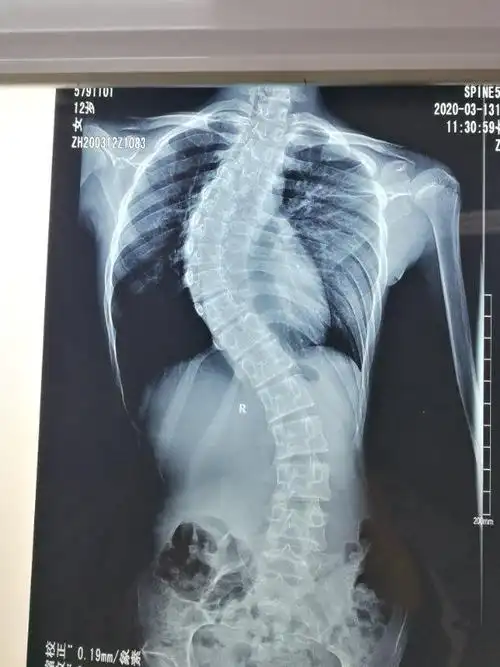

10岁时因为被家长发现双肩不等高,驼背,曾到医院就诊,当时虽然脊柱侧

张慧的背部骨骼变形弯曲,同患此病的哥哥躺在一旁的病床上.